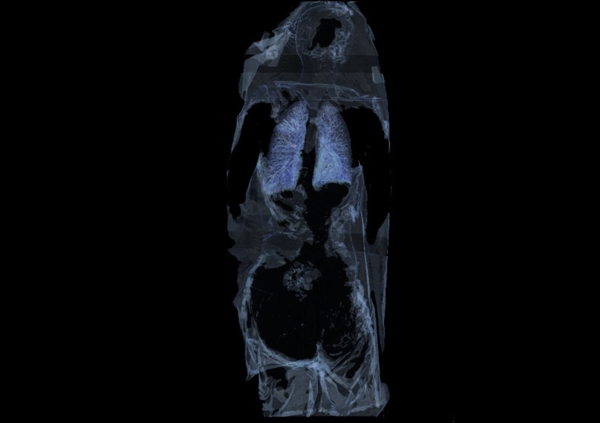

在随后的幻灯片中,您将看到来自瑞典医学图像科学与可视化中心(the Center for Medical ImageScience and Visualization ,CMIV)的Anders Persson和他的同事们运用CT,MRI和超声得到的令人惊叹的尸检图片。这些图片描绘了人体骨骼,消化道,循环系统和大脑以及野猪的前端结构。

6, 人体,正俯视;在有外物包裹的情况下探测内部组织。